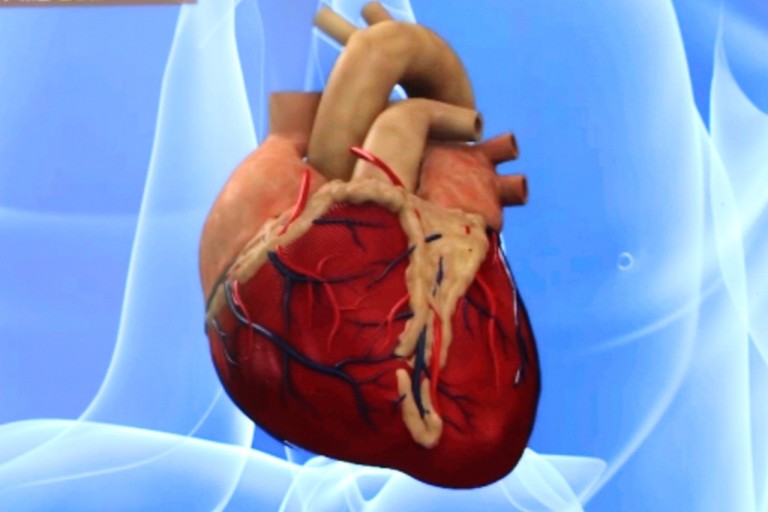

오늘은 정말 많은 분들이 놓치기 쉬운 **치명적인 심장 질환, ‘심근경색’**에 대해 이야기해보려 합니다.심근경색은 말 그대로 심장 근육이 괴사하는 질환으로, 골든타임을 놓치면 생명을 잃을 수 있는 응급상황입니다.

1. 쥐어짜는 듯한 가슴 통증 (흉통)

심근경색의 가장 전형적인 증상입니다.

가슴 중앙 또는 왼쪽 가슴 부근에서 극심한 압박감, 조이는 느낌, 짓누르는 듯한 통증이 나타나며

5분 이상 지속되는 경우가 많습니다. 통증은 휴식으로 사라지지 않고 점점 심해지기도 합니다.